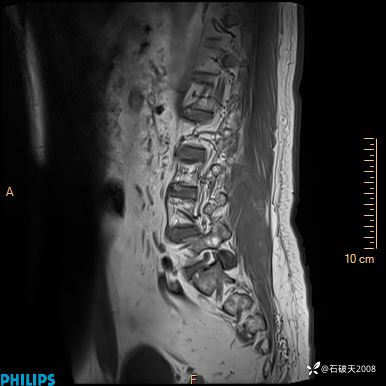

2023年3月份MRI影像

T2矢状位

T2矢状位压脂

现病史:7个月前患者因骶尾部占位就诊于北京大学人民医院,MRI示:骶骨右侧及右骶前占位,考虑骨巨细胞瘤可能,动脉瘤样骨囊肿可能,神经源性肿瘤待排。行手术治疗,术后病理回示:XXXXX。术后给予对症治疗,具体不详,恢复良好。近几个月反复出现发热,伴骶尾部不适,多次住院给予对症治疗,2天前患者无明显诱因再次发热伴骶尾部不适,无大小便失禁,为求进一步治疗,遂门诊来我院,在门诊初步检查后,以“骶尾部肿物”为诊断收入我科。入院来患者神志清,精神一般,饮食睡眠可,大小便无明显异常,体重无下降。